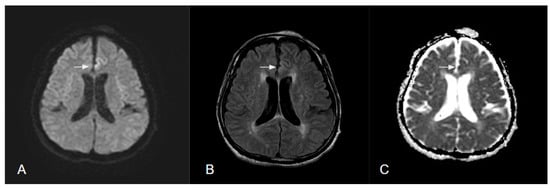

6.1.2. Transient Epileptic Amnesia and Transient Global Amnesia

| Transient global amnesia | - Dot-like hyperintense lesions 1–2 mm in diameter - Commonly in the lateral aspect of the hippocampus (CA-1 region) | Hyperintensity appears with a delay of 24–48 h after onset | Hyperintensities highly detected 2–4 days after onset | |

- You, S.H.; Kim, B.; Kim, B.K. Transient global amnesia: Signal alteration in 2D/3D T2-FLAIR sequences. Clin. Imaging 2021, 78, 154–159. [Google Scholar] [CrossRef]